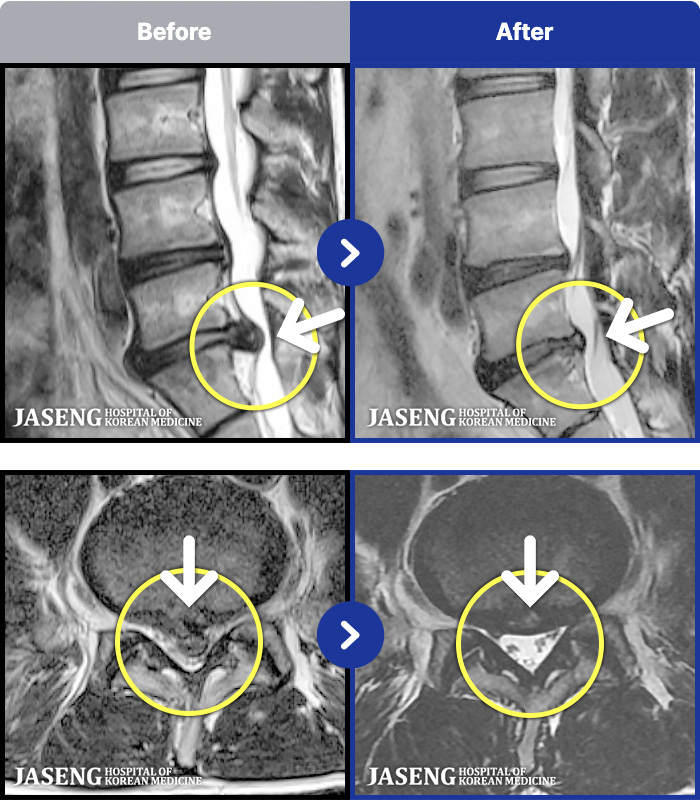

MRI ġ

1,237 MRI ũ ʸ Ȯϼ.

[Ȼ_㸮ũ] 㸮 ְ ٸ ȱⰡ .

[_㸮ũ] 㸮 , ٸ ̾ ϼ̽ϴ.

[õ_㸮ũ] ߲ 㸮 , ٷ

[ϻ_㸮ũ] ݺ ӵǸ ڼ ÿ ȭǴ ߵ ̻ ȣϴ ¿ϴ.

[ϻ_㸮ũ] ؽϰ ߰ ̴ · ϻȰ ¿ϴ.

[ؿ_㸮ũ] 㸮 ϰ

[_㸮ũ] 㸮 ߰ Ͽ ϼ̽ϴ.

[_㸮ũ] Ƹ ߱ ̾ ϼ̽ϴ.

[_㸮ũ] 㸮 ݱ , ٸ Ͽ ϼ̽ϴ.